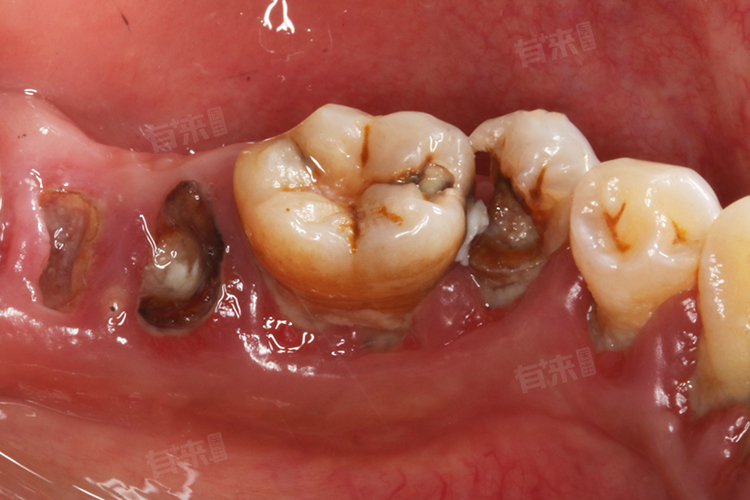

牙齿出现大窟窿且伴有疼痛,通常是由于龋齿未及时治疗,细菌侵蚀牙体组织,累及牙髓或根尖周组织导致。这种情况需根据窟窿的严重程度、疼痛性质及牙髓状态,选择合适的治疗方法,以缓解疼痛、保留患牙、恢复牙齿功能。

- 口腔临床检查:医生首先会对口腔进行全面检查,观察龋洞的位置、大小、深度,查看洞底与牙髓腔的距离,判断牙髓是否暴露。同时检查牙齿的颜色、形态,有无松动,评估周围牙龈组织是否存在红肿、炎症等情况。通过触诊感知龋洞边缘及周围牙体组织的质地,初步判断龋坏程度和病变范围。

- X线检查:通过拍摄根尖片或曲面断层片,可清晰显示龋洞与牙髓腔、牙根的关系,观察根尖周组织有无病变,如骨质破坏、牙周膜间隙增宽等。能发现隐匿在邻面或牙齿根部的龋坏,以及判断龋洞是否累及牙髓,为制定治疗方案提供关键依据,如是否需要进行根管治疗。